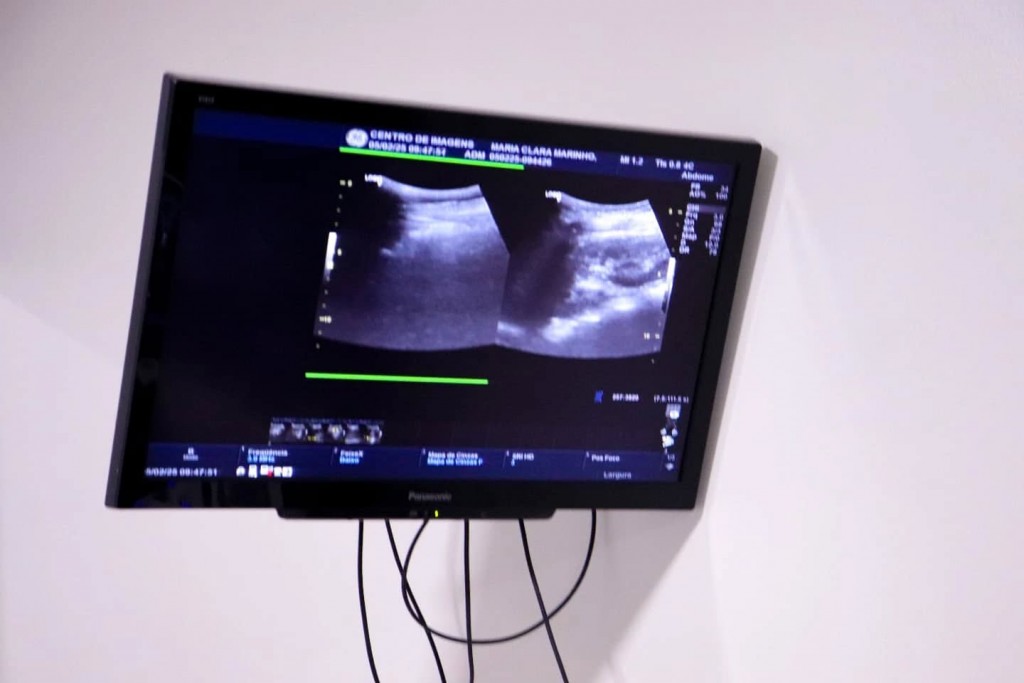

CENTRO DE IMAGENS REALIZA CERCA DE 80 ULTRASSONOGRAFIAS NESTA QUARTA-FEIRA (05)

O Centro de Diagnóstico por Imagens Dr. Felipe Kumamotto segue prestando serviços essenciais à saúde da população, atendendo pacientes de 17 municípios do Sertão e Alto Sertão da Paraíba e do Pernambuco, por meio de pactuações.

Para esta quarta-feira (05), estão agendadas cerca de 80 ultrassonografias, beneficiando moradores de Princesa.